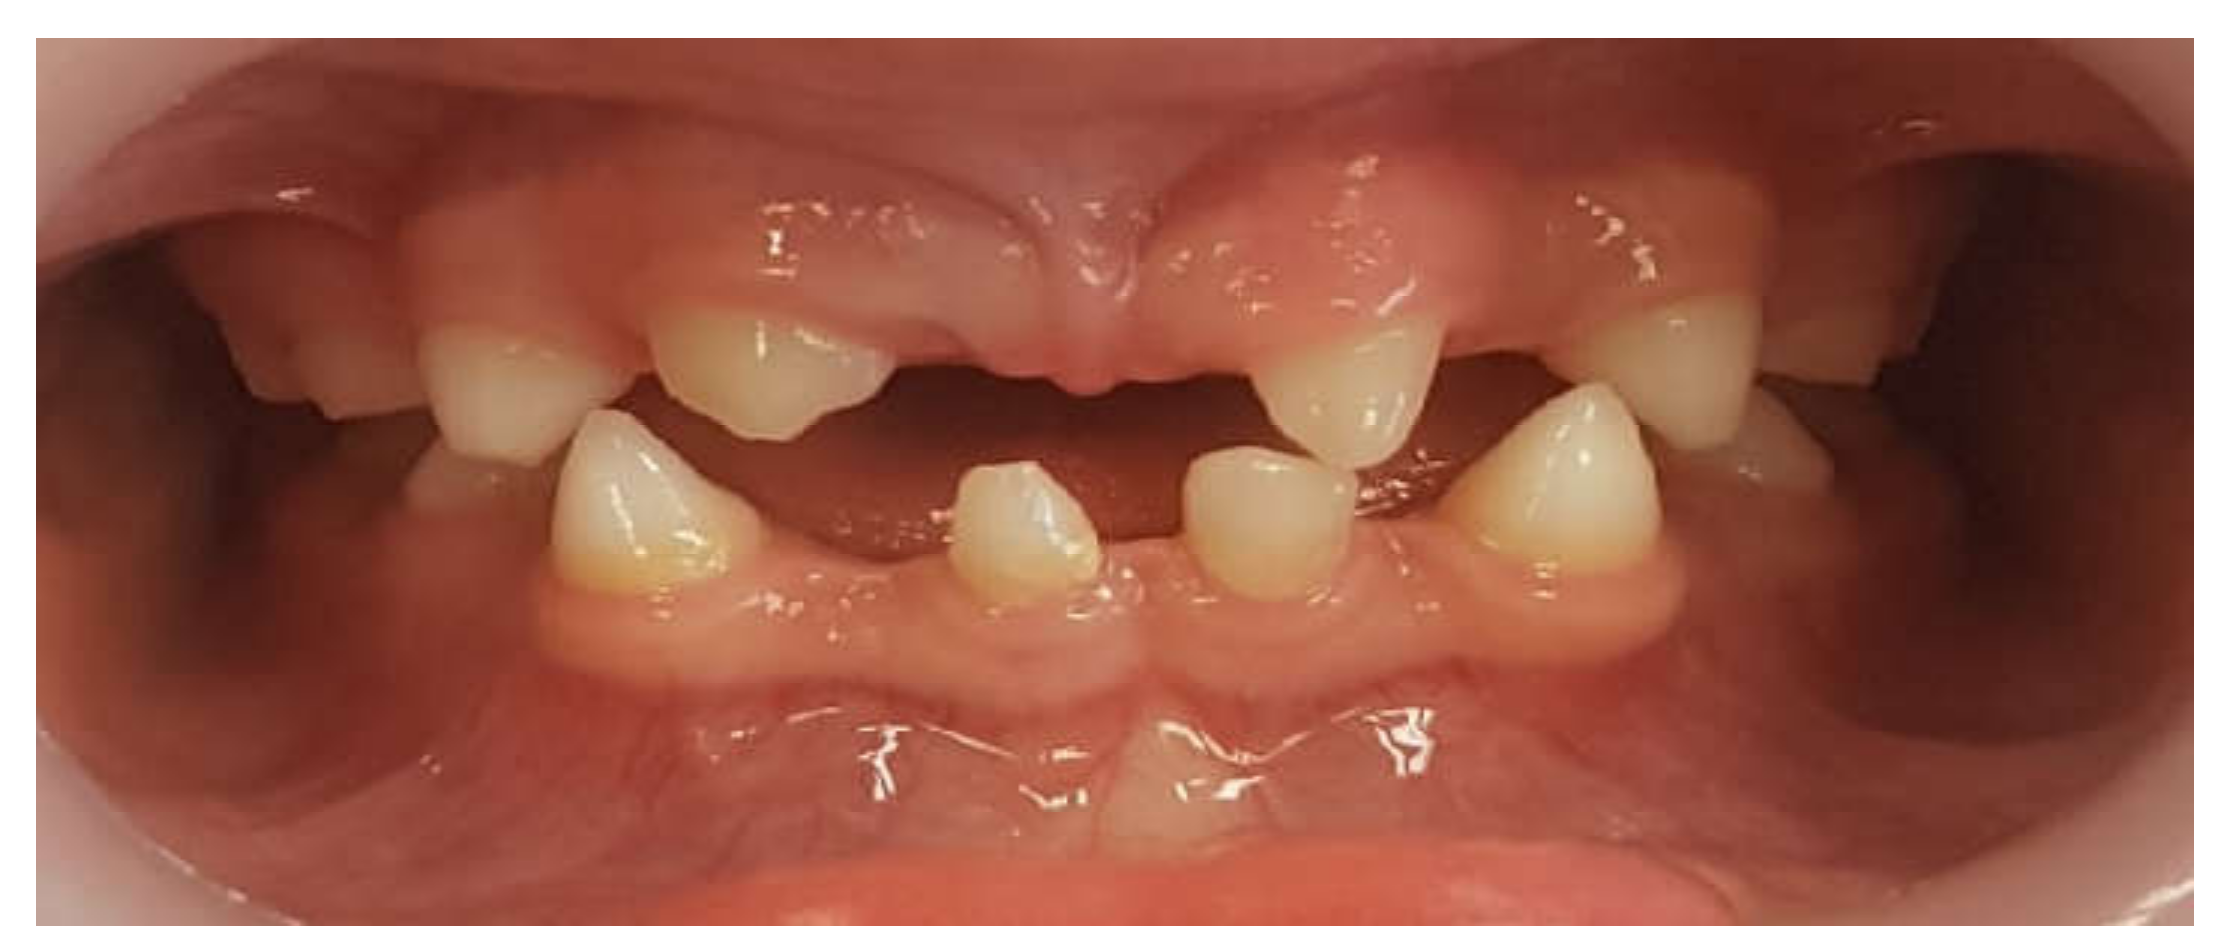

Primary Teeth Supported Fixed Prosthesis—A Predictable Treatment Alternative

2. Materials and Methods

3. Results